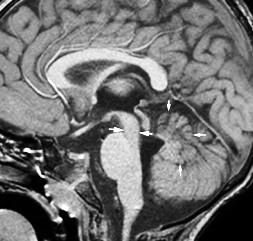

What is the yellow arrow pointing to?

What is the diagnosis?

“molar tooth” midbrain

Large horizontally oriented superior cerebellar peduncles

Small, dysplastic vermis

“bat wing” 4th ventricle configuration

Associated with:

Absence of decussation of WM pathways in brain stem on DTI

Supratentorial:

Absent septum pellucidum

Fused fornices

Ventriculomegaly

Polymicrogyria

White arrows: Small pons remnant with nonformation of the midportion of the brainstem

Clinical: cranial neuropathies

Associated with small cerebellum

Abnormal vertebrobasilar vasculature

Etiology?

very early vascular insult?

No gliosis to suggest hypoxia or ischemia

In animals: seen with hox gene deletions leading to lack of single rhombomere development, so brainstem “short” but typically not fully disconnected